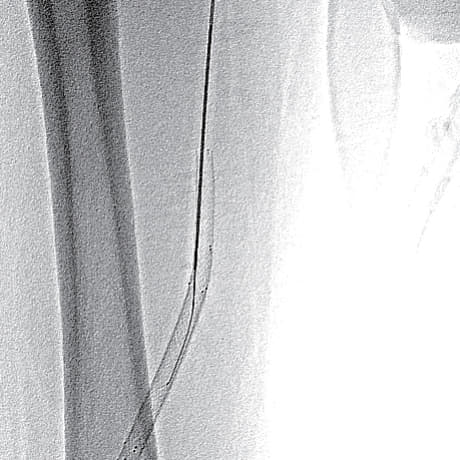

- SFA起始部にわずかなstumpを認め、膝窩動脈のP1-segmentまで連続する閉塞病変あり(図1)